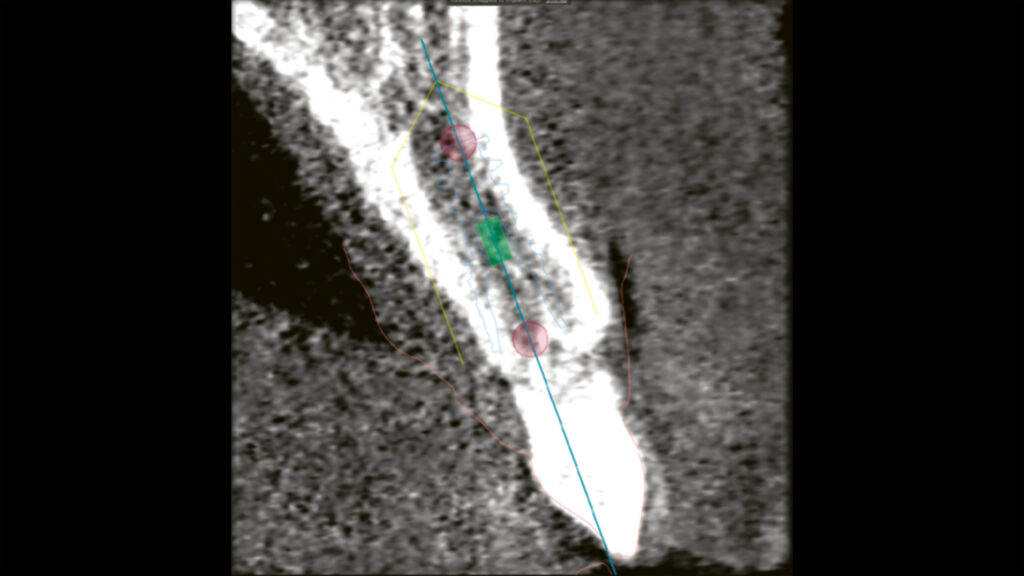

Beim ersten Behandlungstermin wird die Patientensituation mittels DVT/CT (Abb. 3 und 4), intraoralem Scan und klinischen Bildern digital erfasst. Der digitale Workflow von DTX Studio Implant und DTX Studio Lab (Nobel Biocare, Zürich, Schweiz) optimiert die Zusammenarbeit und Kommunikation zwischen den Behandlungspartnern und steigert gleichzeitig die Effizienz der Behandlung. Bei der computergestützten Implantatchirurgie arbeitet der Chirurg mit Software und digitaler Bildgebungstechnologie, um das Implantat effizient und präzise zu inserieren. Zu den Technologien, die in der computergestützten Implantatchirurgie eingesetzt werden, gehören: 3D-Bildgebung, DVT-Scans (Cone Beam Computed Tomography), CAD/CAM-Bildgebung und digitales Röntgen.